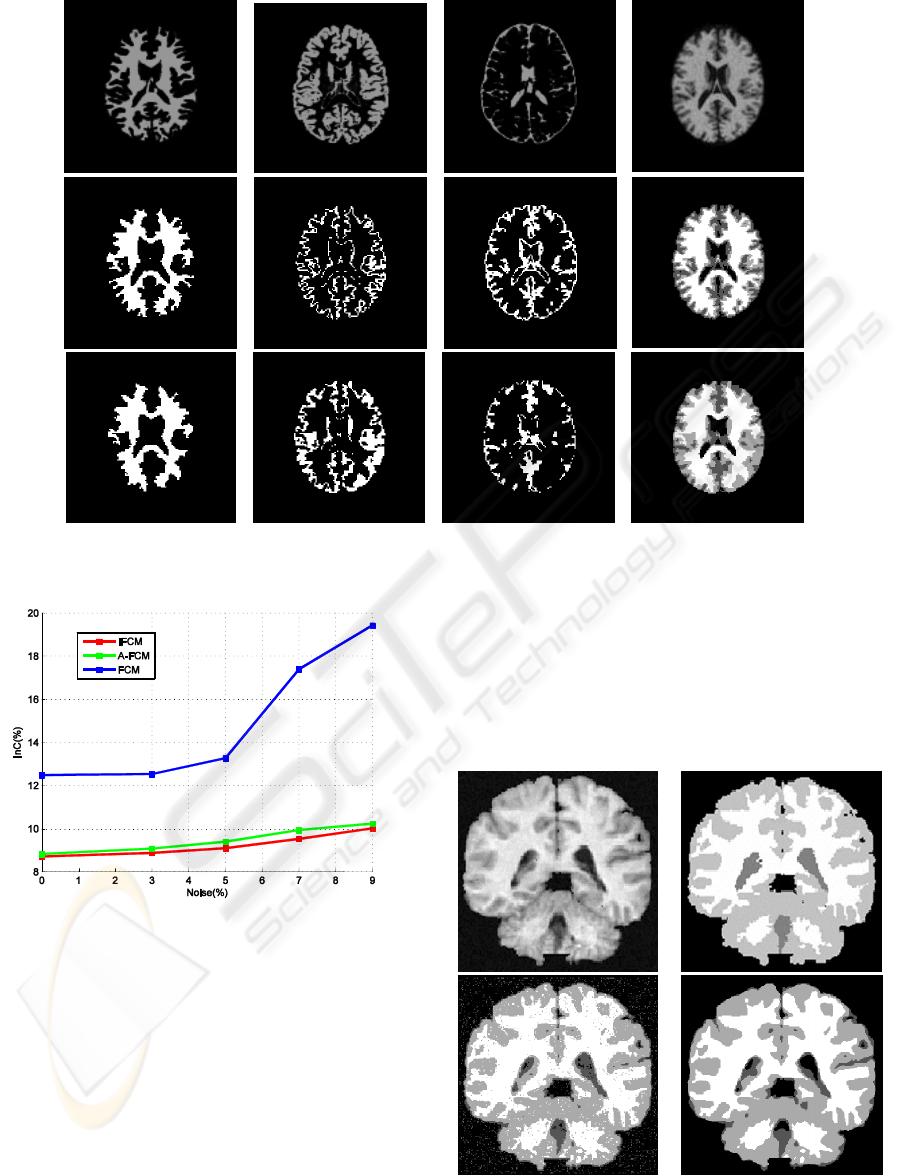

Abstract: Magnetic resonance (MR) imaging is an important diagnostic imaging technique to early detect abnormal

changes in the bain tissues. However, a serious limitation of the MR images is the significant amount of

noise which can lead to inaccuracte segmentation. In this paper, a robust segmentation method based on an

improvement of the conventional Fuzzy-C-Means (FCM) by modifiying its membership function is

realized. A neighborhood attraction depending on the relative location and features of neighboring pixels is

incorporated into the membership function to make the method robust to noise. Simulated and real brain

MR images with different noise levels are used to demonstrate the superiority of the proposed method

compared to some other FCM-based methods.